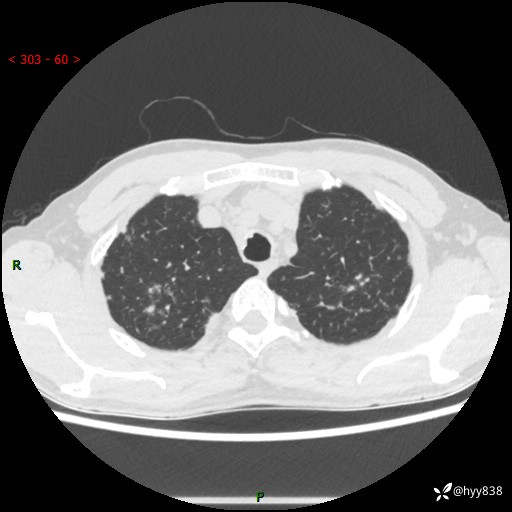

中年男性,咳嗽咳痰1月余。细看:肺、肺门、气管,貌似都有问题---(有结果)

现病史:患者于1个月前受凉后出现间断性咳嗽,伴白色泡沫样痰,无发热寒战、咯血、胸痛胸闷、恶心呕吐、呼吸困难等特殊不适,起初未予特殊处理,后患者就诊当地中医医院,查胸部CT提示支气管炎并双肺感染性病变,经抗感染(哌拉西林舒巴坦),止咳化痰(溴己新、三拗片)等治疗后,患者自诉咳嗽咳痰症状较前缓解,未诉发热等其他特殊不适,近期复查CT提示“肺部感染灶未见消退,双侧肺门增大,双肺散在小结节”,今为求进一步诊治,前来我院就诊,门诊以“肺部感染”收住入院。 患者自起病来精神、食欲、睡眠尚可,大小便正常,体力、体重无明显变化。

胸部CT平扫+增强(两期)